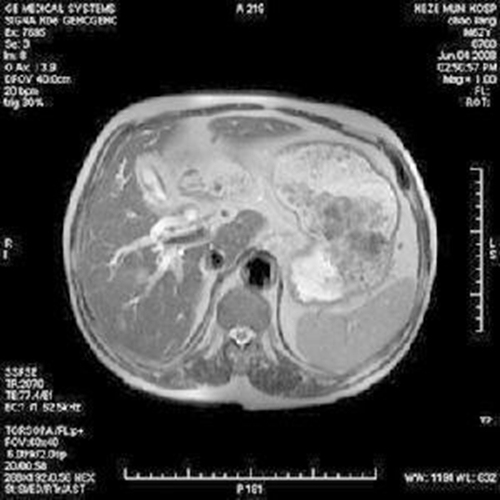

總膽管癌晚期